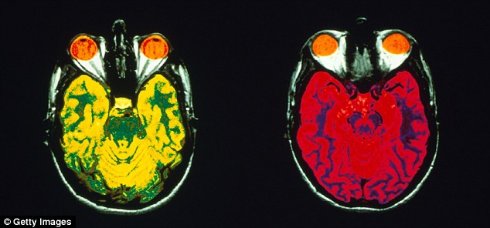

Предыдущие исследования показали, что выработка новых молекул является необходимым условием для хранения воспоминаний в

Исследование на мышах показало, что за блокировку нужных молекул отвечает белок под названием FXR1P (Fragile X Related Protein 1). Его селективное удаление из определенных частей

FXR1P дал удивительный результат. До сих пор никто не мог определить его роль. Наше открытие предоставило фундаментальные знания о процессе обработки информации